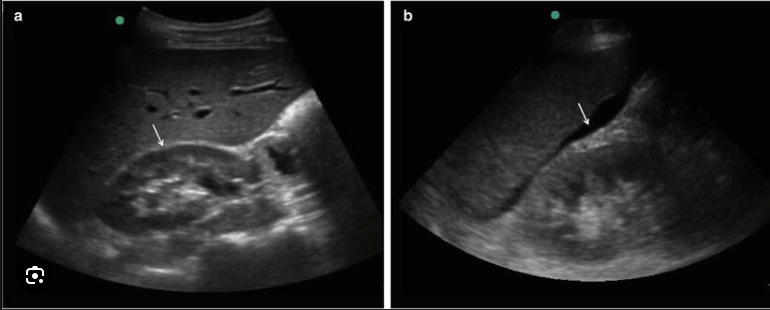

The name of this abdominal US finding.

What is intussussception?